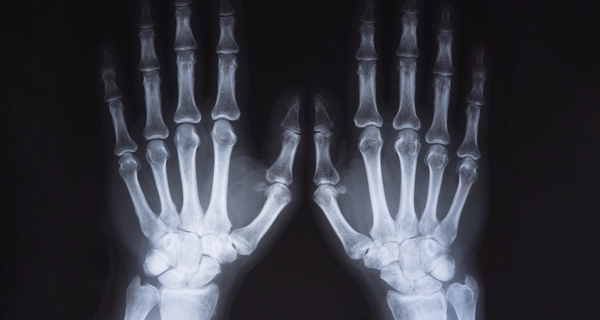

Рентген костей — это информативный и быстрый метод диагностики, позволяющий выявить переломы, трещины, вывихи, деформации и другие изменения костной ткани. Исследование используется для оценки состояния суставов, выявления последствий травм, а также контроля эффективности лечения. Процедура безболезненна, проводится с минимальной лучевой нагрузкой и занимает всего несколько минут.

Рентген костей помогает врачу быстро и точно определить состояние костей и суставов. Исследование проводят при подозрении на:

Снимок даёт чёткое изображение, по которому специалист может оценить наличие повреждений или изменений и назначить правильное лечение.